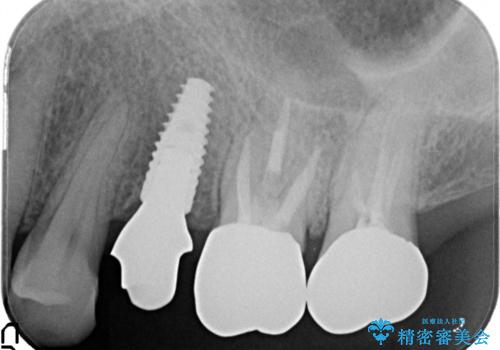

小臼歯部のインプラント

- 他院にて└5の治療を繰り返しても痛みがなくならないことを主訴に来院されました。

患歯はすでに2回の歯根切除術を受けており、長期的な予後不良となることから抜歯を選択されインプラントによる治療を行いました。

└6の不良補綴物も認め、根管治療及び補綴もやり替えてます。